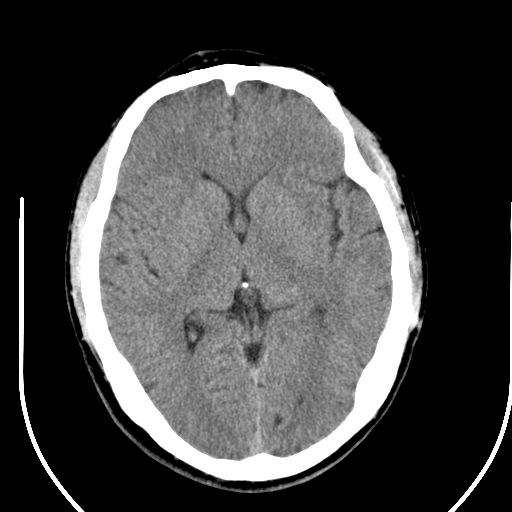

右顶叶低密度影考虑脑沟

边缘清晰,没有占位效应,不像脑沟,结合ct值,软化灶可能吧

与脑沟没关系,小软化灶或陈旧性感染吧!

看样年纪不小了直接报腔梗,当然你要想报软化灶也是一样的

考虑右侧额叶巨腔隙灶;建议必要时行mri检查。